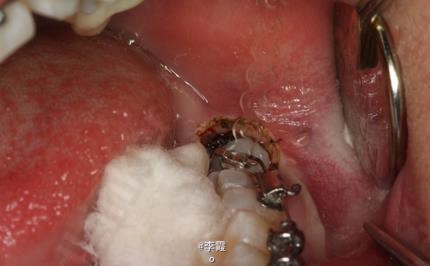

患者、马xx、15岁,主诉:牙齿不齐,要求正畸治疗。 转诊外科行下颌升支处种植体支抗直立下颌磨牙。通过患者的术前影像资料,47牙冠远中有部分骨质覆盖牙冠,采取翻瓣导萌直立磨牙。37采取电刀环切导萌直立磨牙。